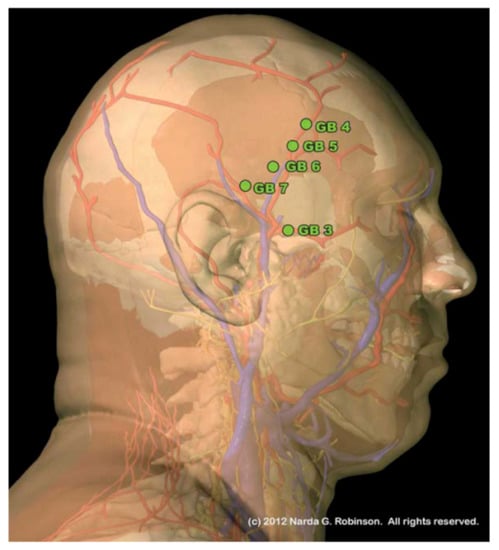

8.1. Head

8.1.2. Temporal Fossa